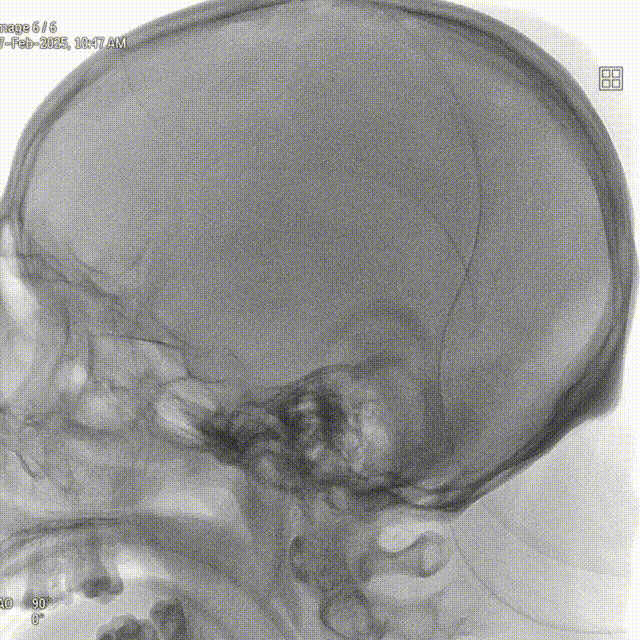

右侧颈内正位造影

右侧颈内侧位造影

载瘤动脉远端血管直径:2.1mm

载瘤动脉近端血管直径:1.8mm

动脉瘤尺寸:瘤颈4.69mm,大小3.25mm*4.21mm*4.24mm;指向右上

近端狭窄:最窄处:0.53mm,远心端2.1mm,近心端2.2mm,长度11.23mm